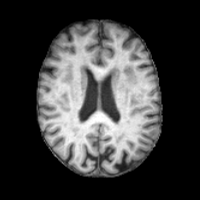

InputUNAOutputEstimatedAnomalyRefer to captionRefer to captionRefer to captionRefer to captionRefer to captionRefer to captionRefer to captionRefer to captionRefer to captionRefer to captionRefer to captionRefer to captionRefer to captionRefer to captionRefer to captionRefer to captionRefer to captionRefer to caption

Figure 5: Visualizations of directly applying UNA’s healthy anatomy reconstruction for anomaly detection. The estimated anomaly is computed as the absolute difference between diseased T1w MRI scans and UNA’s reconstructed healthy anatomy.

UNA’s ability to synthesize diseased-to-healthy anatomy naturally equips it with the potential for application to anomaly detection. To demonstrate its effectiveness, we directly use the reconstructed healthy anatomy from UNA to detect abnormalities. Specifically, we follow the standard evaluation pipeline for unsupervised anomaly detection in medical images [6, 21] and compute UNA’s anomaly estimation maps by calculating the voxel-wise absolute differences between the diseased input and the reconstructed output. The anomaly detection Dice scores are then obtained by comparing the ground truth pathology segmentations with the computed anomaly estimation maps, scaled to the range [0, 1]01[0,\,1][ 0 , 1 ] such that they represent the normalized abnormality. The same procedure is applied to other competing models.

As shown in Fig. 5, UNA’s difference maps clearly identify anomalies with varying shapes and sizes. Quantitative comparisons are provided in Tab. 3, where UNA: (i) outperforms other modality-agnostic synthesis models, and the state-of-the-art anomaly detection models; and (ii) demonstrates consistent performance across various datasets.